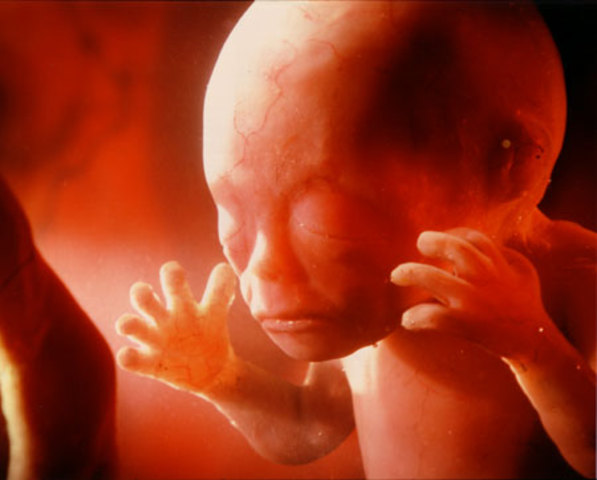

Period of the Embryo

Lasts from 2 weeks after conception until 2 months after conception.

• Month 2

Month 2

Embryo is one inch long, the veins are visible, and the heart is divided into chambers. Mother has increased urination, swelling breasts, and nausea.